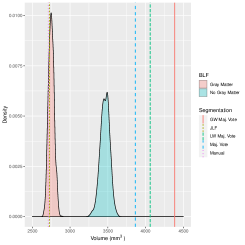

As already mentioned, only healthy brains are used as atlases. The systematic differences are not completely captured by atlas-target image dissimilarities. Despite accounting for image dissimilarity, there is a tendency for the established methods to over-segment the hippocampus. The Bayesian label fusion model facilitates explicit incorporation of the estimated gray matter pattern as a predictor. Our prior specification allows for the possibility that the tissue classes are incorrectly assigned in some places, but are mostly reliable. The effect of the gray matter segmentation as auxiliary information can be clearly seen by comparing it even with our own model in which this information is ignored but the model is otherwise identical. Figure 10 displays the posterior inclusion probabilities obtained without using the gray matter information, along with the results already presented for reference. Using only the intensity-similarity-weighted distance labels yields a Bayesian regression analogue to the other approaches that only weight by intensity similarity. The additional tissue class information is able to prevent oversegmentation of the diseased structure.

In practice, an anatomical structure is segmented to obtain important information such as its volume or average image intensity within the structure. In our case, segmenting the hippocampus is a step toward estimating its volume. If we only obtain a binary map, then the only way to estimate the volume is by summing the indicators. Doing so ignores many sources of uncertainty, including image pre-processing, registration error, biological variation, and rater variability. Monte Carlo sampling also facilitates estimation of a distribution of plausible volumes through , defined in Section 3. Figure 11 displays the marginal volume densities for the diseased brain of interest, both with and without gray matter included in the Bayesian label fusion model. Vertical lines indicate the manually-segmented volume and the volume estimates from the other procedures considered. The benefit of including the gray matter information is again evident with the improved agreement of the volume distribution with the manual segmentation. In this case, though, we see that even without the gray matter information the Bayesian model outperforms the three majority voting procedures.